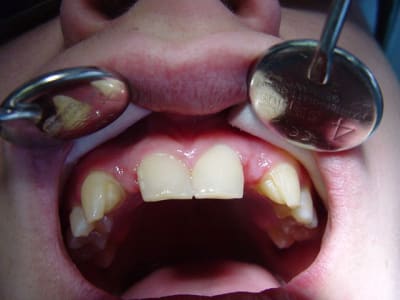

29/12/2010 à 22h41

résultat premier bridges collés Emax

à voir dans le temps...

gestion du temps provisoire pas évident

surtout sur un étudiant présent que le WE..

et encore désolé pour l'iconographie (pas ma préoccupation majeure car un peu pris ds le rythme .. )

ça a vraiment le mérite d'avoir ete tenté , bravo ! surtout sur un etudiant , patient à vie risquée (sandwich, barre cereales etc ...) donnera une bonne idee du futur .

et puis le résultat est top compte tenu de la situation spaciale des collatérales ...beaux rendu de teinte et aussi du collage des canines ...

Pourquoi ne pas avoir "travaillé" plus les embrasures, la papille va pas etre contente.

fraise tungstène spéciale c'est encore faisable, sans compromettre la solidité.

belle teinte.